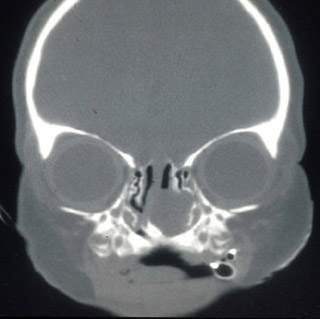

This coronal CT scan illustrates a left intranasal mass extending from the anterior cranial fossa. Child with unilateral intranasal masses may have congenital intracranial communication.